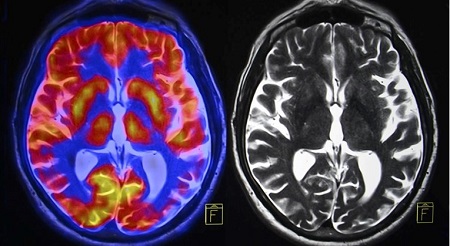

Научниците спроведоа магнетна резонанца на испитаниците за време на три менструални фази: менструација, овулација и средна лутеална фаза. Тие го мереле и нивото на хормоните. Резултатите покажаа дека како што флуктуираат хормоните, волуменот на сивата и белата материја, како и волуменот на цереброспиналната течност се менуваат.

Конкретно, непосредно пред овулацијата, кај испитаниците е забележана промена на белата маса, што укажува на побрзо пренесување на информации. Хормонот за стимулирање на фоликулите, кој се зголемува пред овулацијата и помага во стимулирање на фоликулите на јајниците, беше поврзан со погуста сива материја. Прогестеронот, чие ниво се зголемува по овулацијата, е поврзан со зголемување на ткивото и намален волумен на цереброспиналната течност.